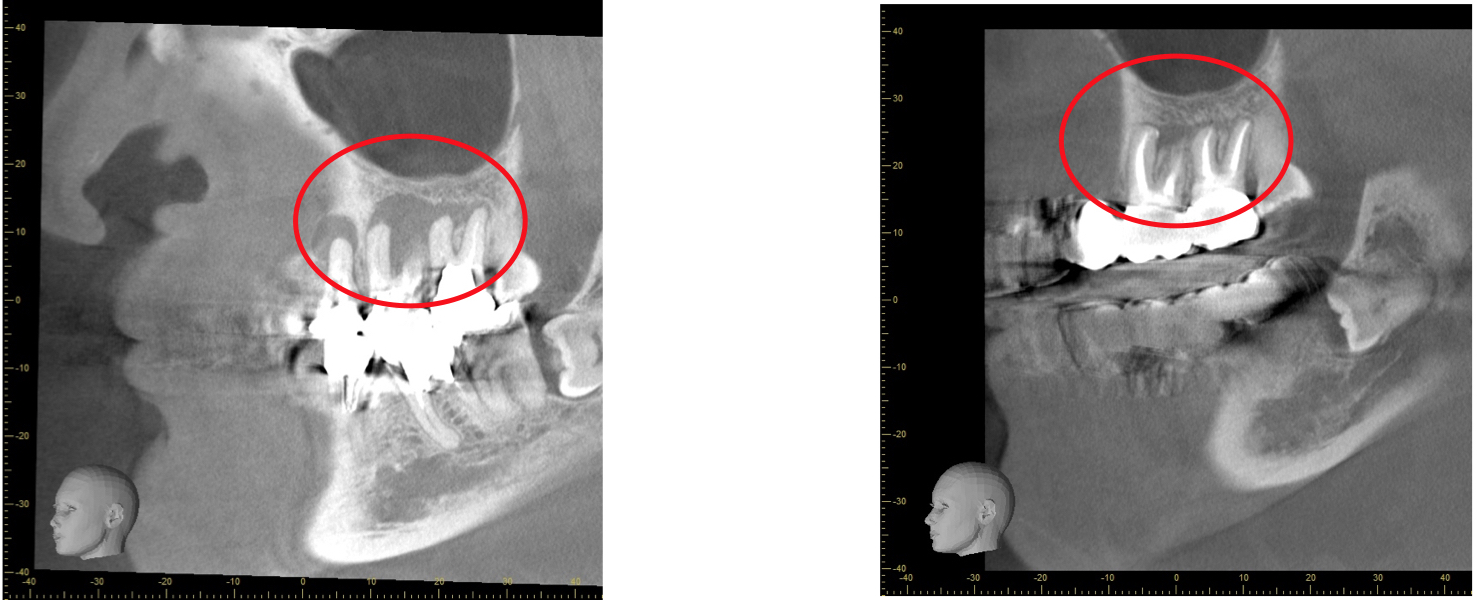

歯科用CTとは一般の医療用CTを歯科治療用に特化した装置です。

当院ではこの歯科用CTを使用して三次元で歯の構造を把握します。

任意の角度や位置から歯・顎骨を確認することもできるので治療の精度が大幅に向上します。